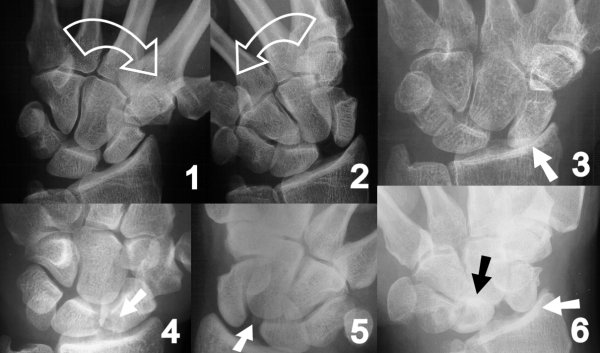

Figure Legend:

Scapholunate dissociation may require dynamic stress views to

demonstrate (1,2). The natural progression of scapholunate dissociation

is a pattern of wrist arthritis involving the radioscaphoid and

capitolunate joints, referred to as ScaphoLunate Advanced Collapse or

"SLAC wrist" (3, 6). Very proximal scaphoid avulsion fractures (4,5)

are mechanically similar to scapholunate ligament injuries.